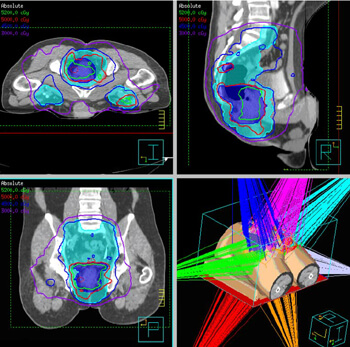

첫째, 치료 계획을 수립합니다. IGRT를 시작하기 전에, 환자는 CT, MRI, PET와 같은 영상 진단 장비를 통해 정밀한 영상을 촬영합니다. 이 영상들은 종양과 주변 정상 조직의 정확한 위치와 형태를 파악하는 데 사용됩니다. 이 데이터를 바탕으로 의료 팀은 개별 환자에 맞는 맞춤형 방사선 치료 계획을 수립합니다.

넷째, 치료 계획을 실시간으로 조정합니다. 실시간으로 획득한 영상 정보를 바탕으로, 치료 계획은 필요에 따라 조정될 수 있습니다. 종양의 위치가 이동했거나, 환자의 체형 변화 등이 감지되면, 방사선의 방향, 강도, 조사 영역 등이 실시간으로 수정됩니다. 이 과정은 치료의 정밀도를 극대화하고, 정상 조직에 대한 피해를 최소화합니다.

둘째, IGRT는 종양과 주변 정상 조직의 위치를 3차원적으로 정확하게 파악할 수 있으며, 환자의 호흡이나 움직임에 따른 변화까지 고려하여 치료를 진행합니다. 이는 종양에 대한 방사선의 조사 정확도를 크게 향상시키며, 결과적으로 치료의 성공률을 높입니다.